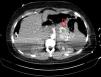

La paciente es trasladada a la Unidad de Cuidados Intensivos con una hemoglobina de 5,8g/dl y un hematocrito de 16,8%. Se transfunden 3 concentrados de hematíes y 3 unidades de plasma fresco congelado, tras lo cual la hemoglobina es de 7,2g/dl y el hematocrito del 22%. Se realiza una angio-TC, en la que se visualiza como posible origen del hemoperitoneo una dilatación aneurismática de la arteria esplénica de unos 3cm (fig. 1).